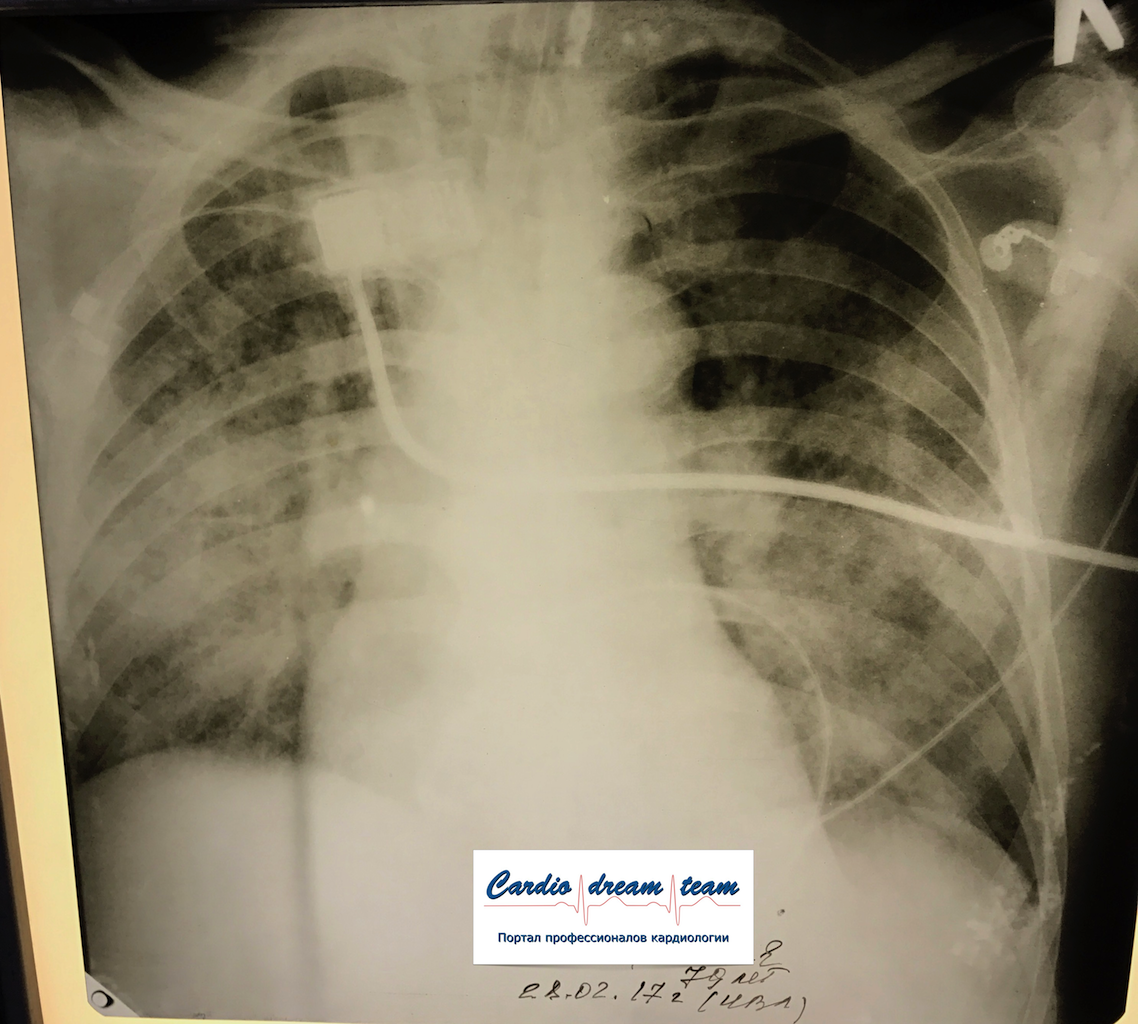

Не обсуждалась Дата 23-ИЮЛ-15 ОПИСАНИЕ: Проведена рентгенография органов грудной клетки в прямой проекции, положение лежа, условия ПИТ Легочные поля: неравномерно прозрачны за счет сосудистого обогащения, в базальных отделах с обеих сторон, отмечается сгущение легочного рисунка, за счет гиповентиляции, в плевральных полостях жидкость Легочный рисунок: Изменен по смешанному типу: обогащен за счет сосудистого компонента, деформирован за счет склероза. Корни: бесструктурны, расширены за счет сосудистого компонента, обогащены Синусы: определяется наличие жидкости по линии 5 ребра Сердце: широко лежит на диафрагме отмечается расширение границ сердечной тени влево, вправо экг-электроды. ЗАКЛЮЧЕНИЕ: Рентген-признаки 2-х стороннего гидроторакса с гиповентиляцией базальных сегментов.. Признаки застоя по МКК 2 степени (умеренно выраженный). Пневмосклероз. Р-признаки гипертрофии левого желудочка сердца. Склероз аорты.